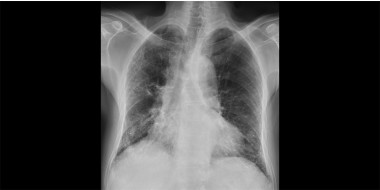

Longfibrose [Kennistoets]